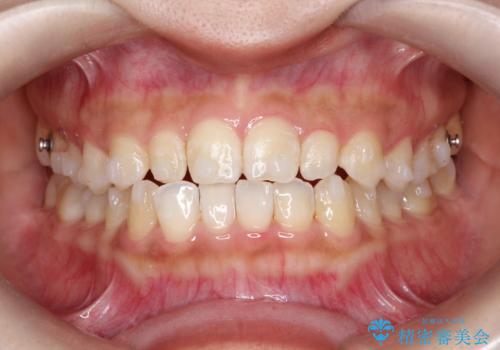

- 前歯の凸凹を主訴に来院された患者様です。

カウンセリング時に、側切歯が矮小歯であることを指摘したところ、適切な幅径での修復を希望されました。

インビザラインを用い、計画通りに歯並びを改善することができました。